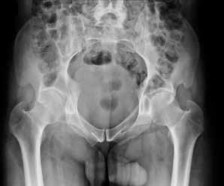

Figure 7Figure 7 is the pelvic radiograph of a 33-year-old man involved in a high-speed automobile crash. Examination reveals a blood pressure of 90/50 mm Hg and a pulse rate of 120/min. Radiographs of the chest and lateral cervical spine are normal. A CT scan of the abdomen does not reveal any intraabdominal bleeding. What is the most appropriate management for the pelvic fracture?